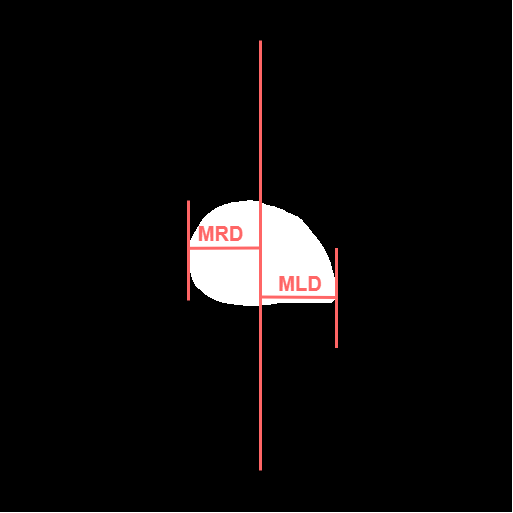

3.5 Cardiothoracic Ratio Calculation

After obtaining the masks, we calculate CTR with equation 1. We calculate cardiac diameter, , by finding the extreme points on the x-axis of the heart mask and calculate their x-axis distance. Thoracic diameter, , is calculated from extreme points from the lung mask. Figure 4 demonstrates the calculation of each component.